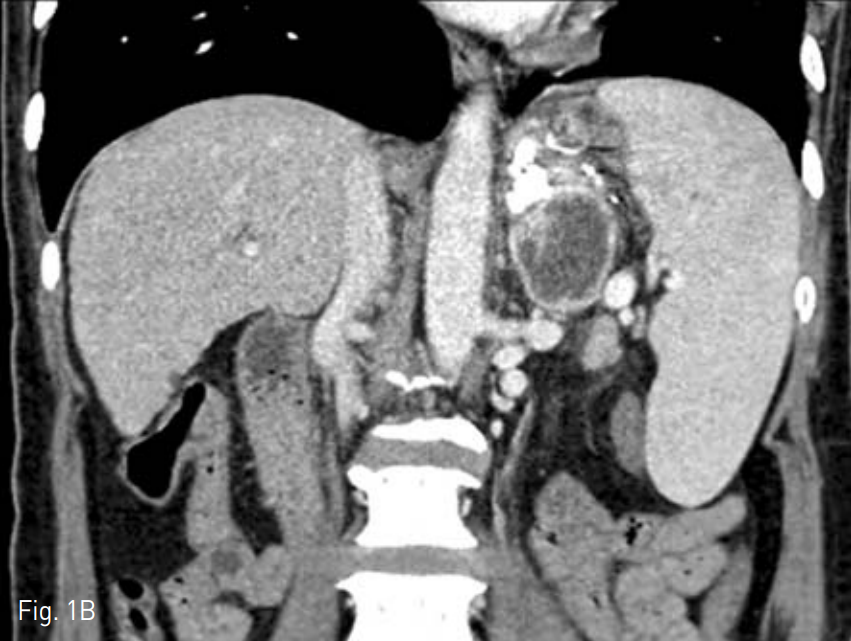

조영증강 전산화 단층촬영술 상 위 기저부에 정맥류 차단술을 시행한 것이 관찰되며 이와 이어지면서 좌측 전방 신 주위 공간에 4cm 크기의 농양이 관찰되었다(Fig. 1A, B).

Contrast enhanced axial (A) and coronal (B) CT scan shows 4cm sized abscess at left anterior pararenal space.